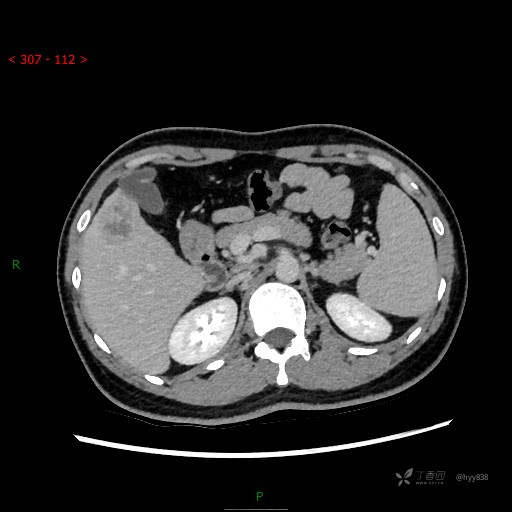

年轻男性,肝脏孤立结节、邻近包膜如此内陷,不知“坑”为何物---(结果公布)

简要病史: 患者1月余出现腰背部疼痛,以夜间疼痛为甚,伴双下肢胀痛,无腹胀、腹痛,无咳嗽、咳痰,无头晕、头痛等症状,门诊超声提示肝结节状占位

临床诊断:肝占位

门脉期